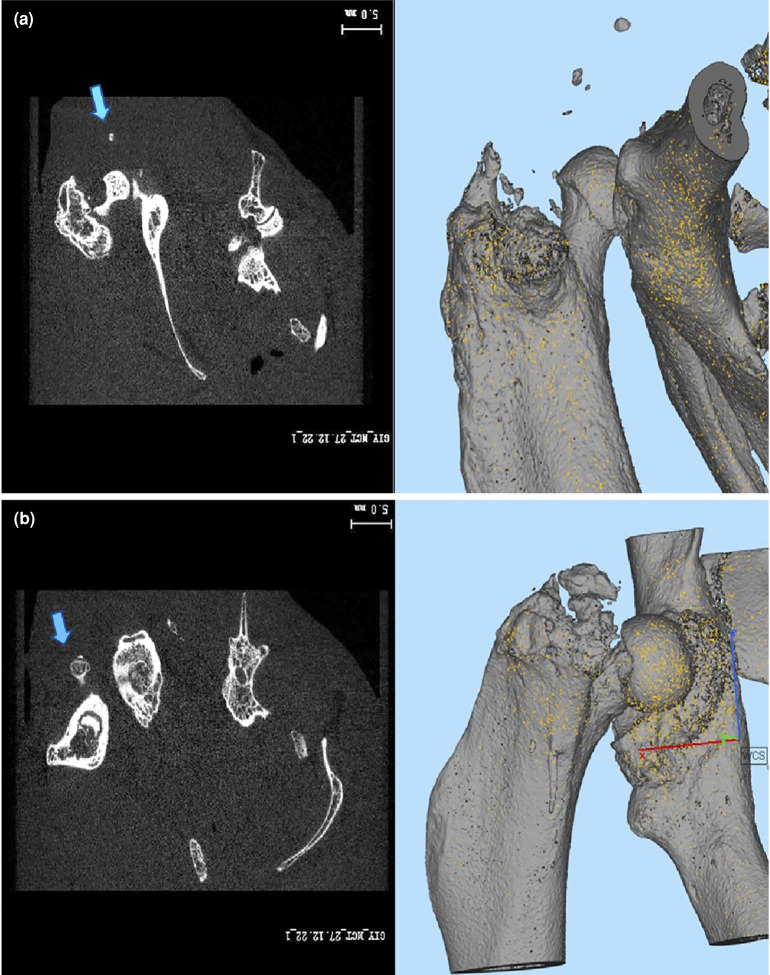

Results: The modified Brooker staging method was used for radiological evaluation, and all animals in the control group showed at least Stage 1 HO formation. However, only three animals (30%) in the OT group showed HO formation (p=0.006). In histopathological evaluation, the median HO rates in the high power field were 42.5 (range, 30 to 55) in the control group and 0 (range, 0 to 25) in the OT group (p=0.003), and the median leukocyte count was 5.5 (range, 3 to 7) in the control group and 1 (range, 0 to 3) in the ozone group (p=0.006). Radiological HO, histopathological HO, and inflammation were significantly lower in the ozone group (p<0.05).